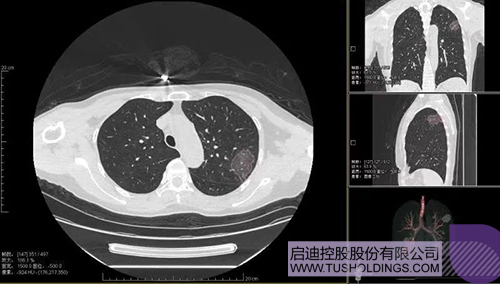

2020年2月11日,乐动在线科服投资企业—神州德信推出新冠肺炎检测及量化智能分析系统,积极助力一线医务人员科学精准防疫。